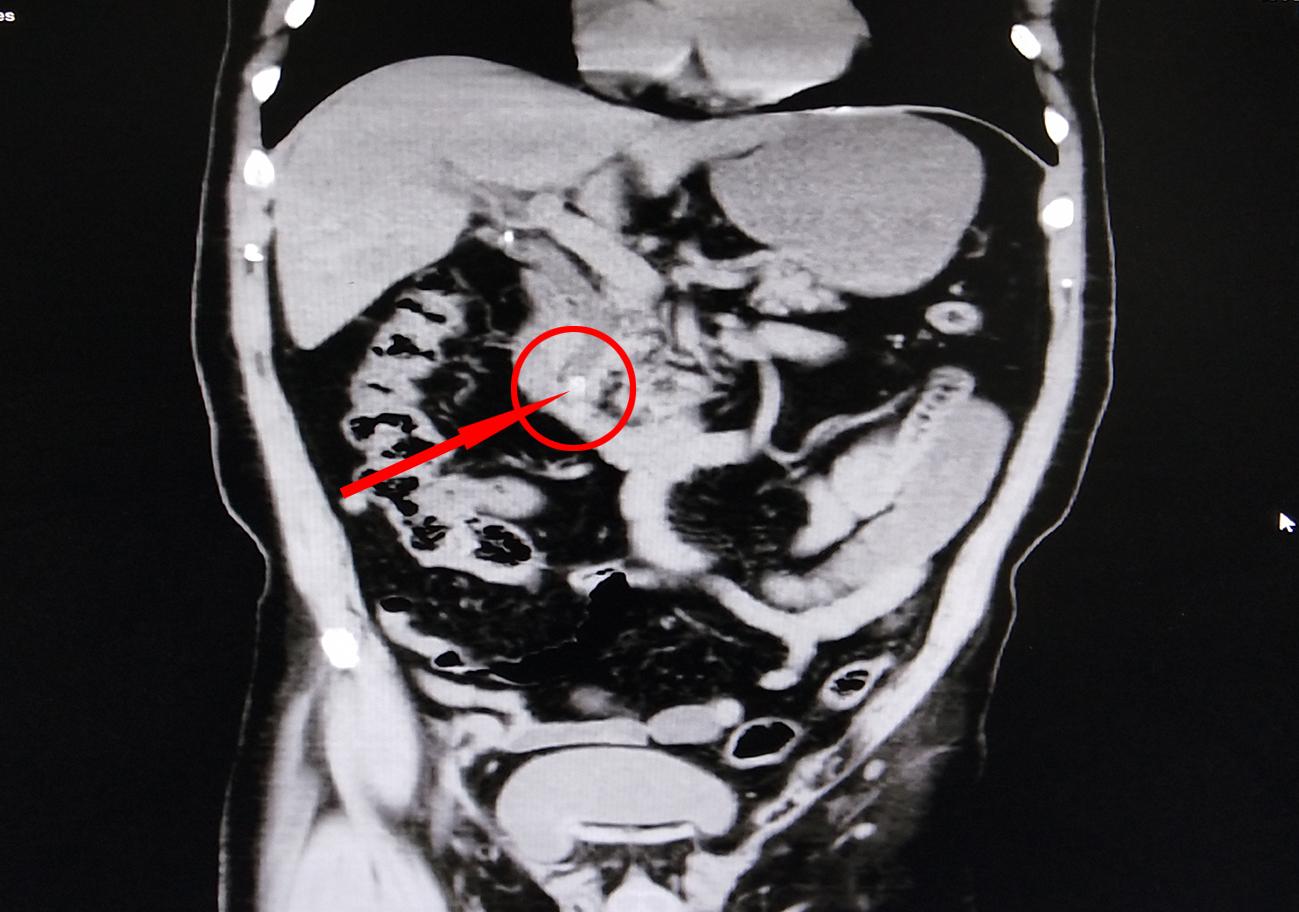

荆门二医消化内一科副主任医师张林一边积极退热等对症治疗,一边急查相关指标,以明确诊断。直接胆红素48.8umol/L(参考值0-8umol/L)、谷丙转氨酶414U/L(参考值9-50 U/L)、白细胞14.28×109/L(参考值4-10×109/L)……严重异常的指标及CT确诊为“胆总管结石伴急性化脓性胆管炎”,更棘手的是在血液培养中发现了“大肠埃希菌”, 意味着老刘不仅仅是结石这么简单,感染化脓性细菌已通过血液扩散至全身,急性起病、加重快,一旦引起多脏器损伤,死亡率非常高。

▲老刘CT影像:红圈内小白点为胆总管结石